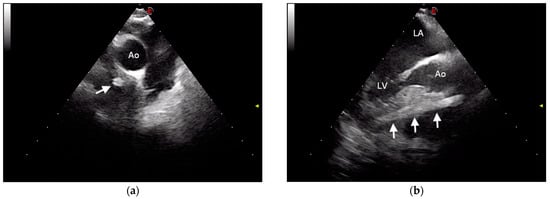

2.1. Case Description and Clinical Investigations